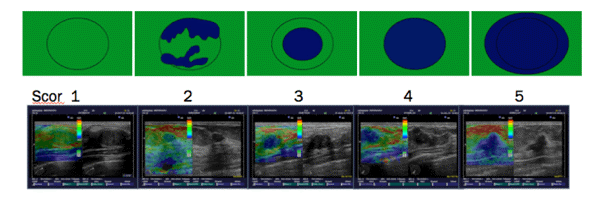

Strain elastography – historically is the earliest elastography technique, where external tissue compression is applied and comparison between ultrasound images and images after compression. The least deformed are the most rigid areas of the image, and the most deformed areas are the softest (7) (Figure1).

Elastography is based on the fact that in malignant tumors the density of cells increases, which changes the elasticity of the tissue itself. Elastography provides an assessment of the deformation of all tissues (fatty, fibroadenomas, or solid lesions) and shows in real-time that benign nodes such as fibroadenomas, papillomas, etc. (Figure1). In malignant lesions, there is a certain inelasticity of the tissue, which is usually the result of neoplastic infiltration of the interstitium, the desmoplastic reaction intra- and extra-nodular. Such is the case with ductal carcinomas, squamous type of carcinoma. Exceptions are some tumors of the mucinous or papillary carcinoma type which are of low malignant consistency.

Figure1. Elastography shows in real-time benign nodes such as fibroadenomas and papillomas.

To determine the elasticity of changes, the Tskuba score was used with a rate from 1 to 5 (13, 14) (Figure 2).

Figure 2. The risk of malignancy increases from 1 to 5.

Tskuba score

Score 1: if the lesion is homogeneously elastic, completely green,

Score 2: if the larger lesion is deformable green, and only small parts of the areas are not deformed and are blue,

Score 3: deformable on the periphery of the lesion, and the center is rigid, blue,

Score 4: non-deformable blue lesion,

Score 5: lesion and adjacent tissues are stiff and blue.

According to Tsukuba score, almost all categories 1-3 are benign, and categories 4 and5 are malignant.